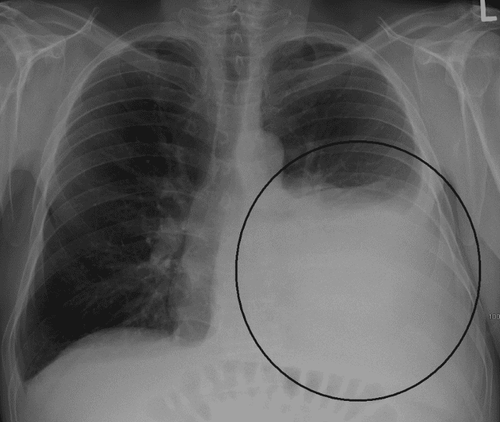

Siêu âm màng phổi là kỹ thuật có khả năng chẩn đoán hiệu quả các bệnh lý tại màng phổi như khối u, viêm, tổn thương... Ngoài ra, siêu âm màng phổi còn được đánh giá cao trong việc phát hiện tràn dịch màng phổi, kiểm tra độ dày màng phổi và khối u trên màng phổi, giúp định hướng chọc dò, sinh thiết màng phổi, dẫn lưu dịch.

Siêu âm mang lại hiệu quả cao trong việc phát hiện và chẩn đoán tràn dịch màng phổi